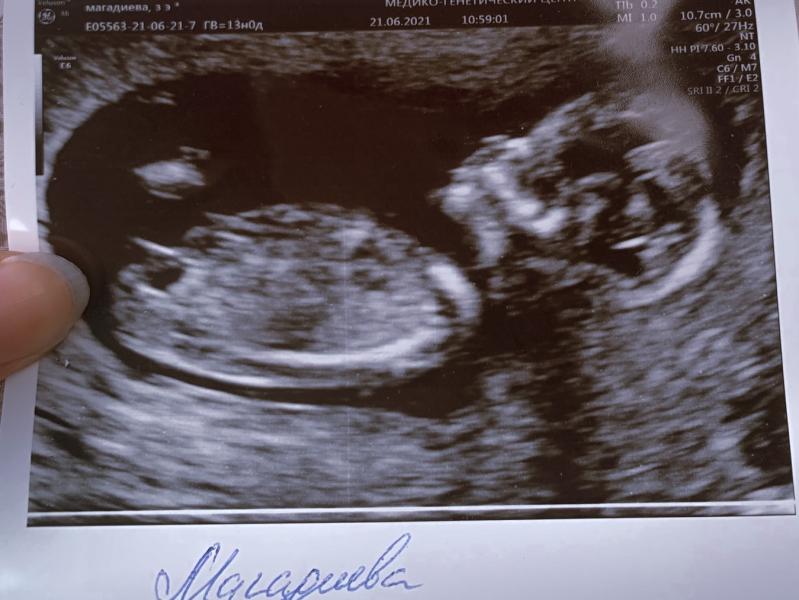

Знакомьтесь пузожитель

Первый триместр закончился и я впервые встретилась с крошкой.

И как я растрогалась, когда увидела на экране голову, тело, ножки и ручки🥰